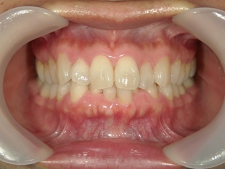

矯正歯科 治療後矯正歯科 プチワイヤー矯正 治療後矯正歯科(プチワイヤー矯正)治療後

矯正歯科 治療後 ミニインプラントを2本埋入し、下顎前歯を圧下